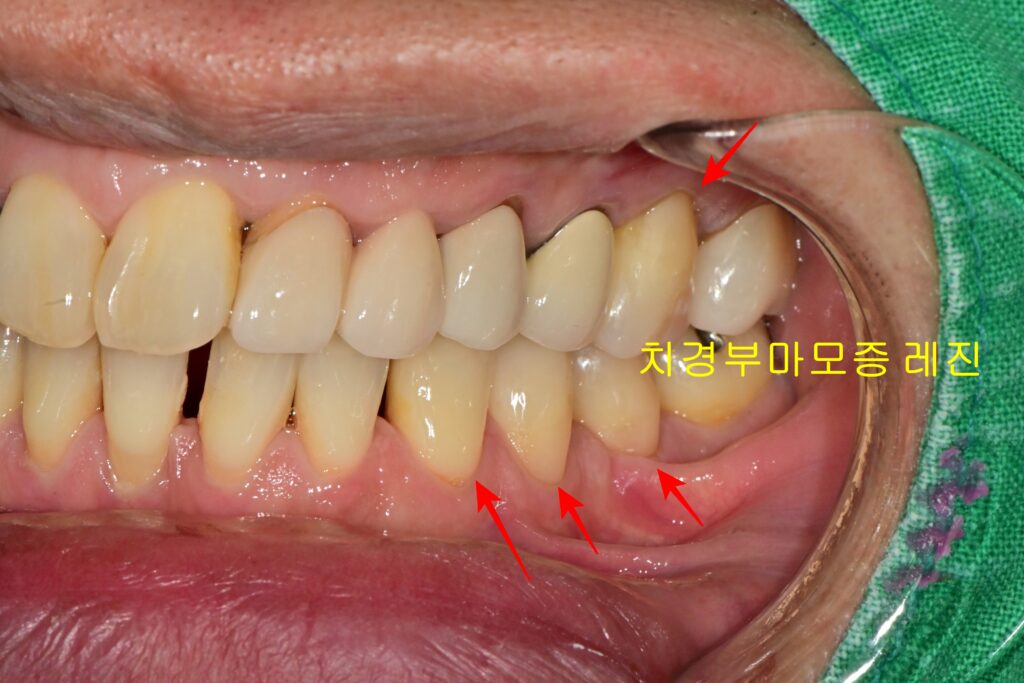

2-1. 치경부마모증이란?

특히 이 치아는 잇몸이 내려가면서 치아 뿌리가 드러났고, 잇몸 경계 부위가 패여 있는 치경부마모증까지 겹쳐 있었습니다.

- 증상: 치아 목 부분(치경부)이 패여서 신경이 노출되거나, 심하면 치아가 부러질 수 있습니다.

- 원인: 잘못된 양치 습관, 이갈이, 교합력 등 다양한 원인이 있습니다.

- STEP 2 (레진 충전): 잇몸이 내려가 드러난 치아 뿌리(치경부마모증) 부위는 **레진(Resin)**으로 꼼꼼하게 메워줍니다.

- 치경부마모증: 패인 치아 뿌리는 레진으로 때워 시린 증상과 파절을 예방해야 합니다.